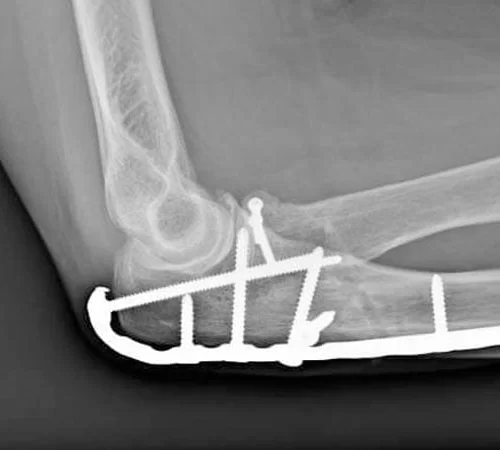

Dirsek Cerrahisi